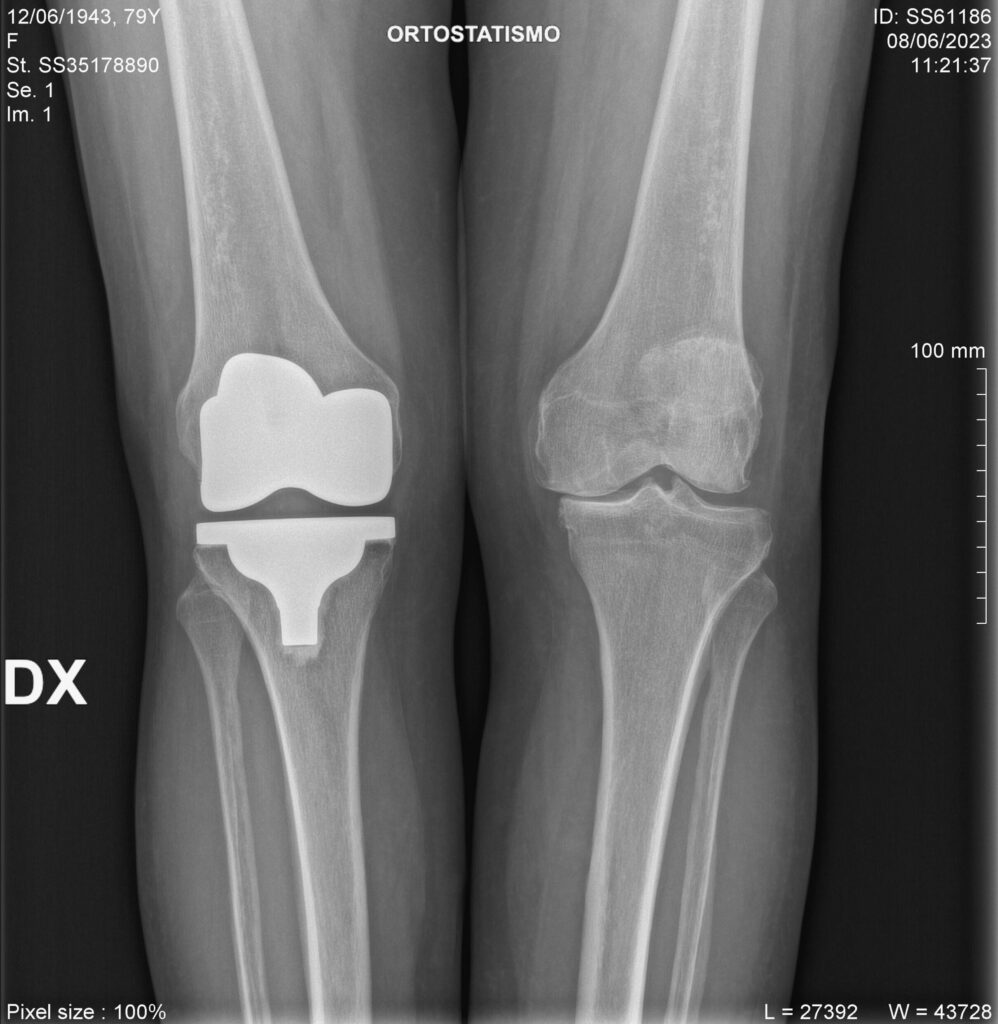

Rx preoperatoria

Rx postoperatoria

Protesi monocompartimentale

In casi selezionati può essere utile l’impianto di una protesi monocompartimentale, considerata la vera protesi di ginocchio mininvasiva. Prevede infatti la sostituzione del solo compartimento danneggiato con componenti protesiche di superficie che rivestono il condilo femorale e l’emipiatto tibiale (mediale o laterale).

Questo tipo di protesi è indicata nell’osteonecrosi del condilo femorale o dell’emipiatto tibiale e nell’artrosi monocompartimentale (che interessa solo una parte del ginocchio, quella mediale o quella laterale).

L’intervento prevede un’incisione di circa 7-8 cm; il decorso postoperatorio è meno impegnativo rispetto a un’artroprotesi totale e il recupero riabilitativo più veloce.